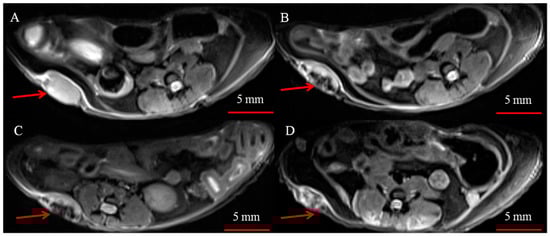

2.2.6. MRI

3.2. Biodistribution of Iron Oxide Core of MNP-HSA@PS